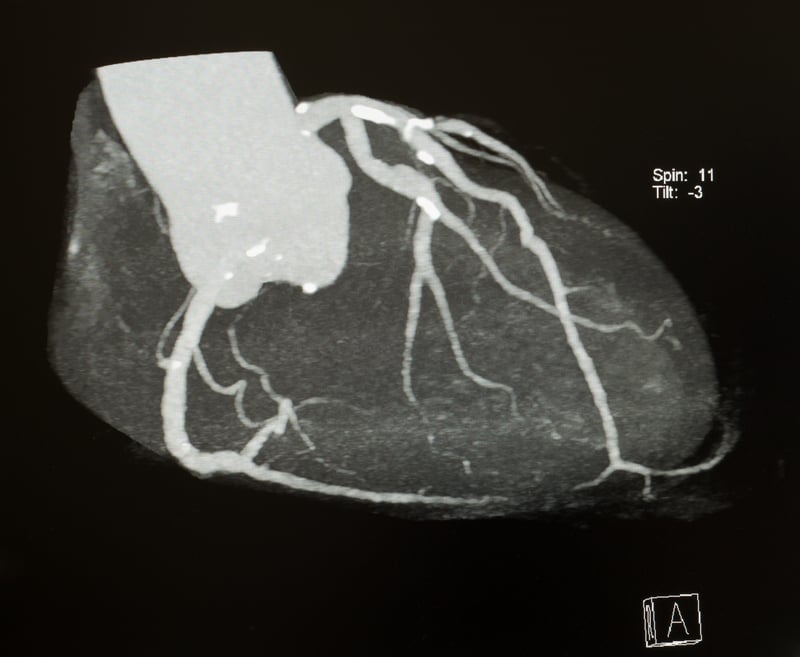

From Detail to the Whole Picture: What the Model Sees

“Most currently available software analyzes coronary images by dividing them into small segments and extracting volumetric measurements. Our approach is entirely new. It uses the full CT dataset, analyzing subtle image variations that might seem insignificant but actually reflect processes occurring within the heart—processes involving moving, interacting, and dying cells and molecules. These details, invisible to the naked eye, are crucial because they tell us what may happen in one, two, three, or four years, allowing us to intervene and change the clinical course of each individual,” Esposito says.

To better understand this, imagine observing three paintings depicting the same hilly landscape, each created by a different artist. Each painting will have distinct brushstroke shapes, directions, and colors that reveal the artist’s unique hand. The AI, by observing the painting as a whole, can read these details and tell us who the painter is.

“What our model does,” Esposito continues, “is observe the whole picture—the CT image of the heart and coronary arteries—and detect the subtle nuances that represent the signature of biological processes occurring at the cellular and tissue level, processes that underlie a future heart attack. Based on what it has learned, the model can then say: given this pattern, there is a certain probability that this patient will have a heart attack.”